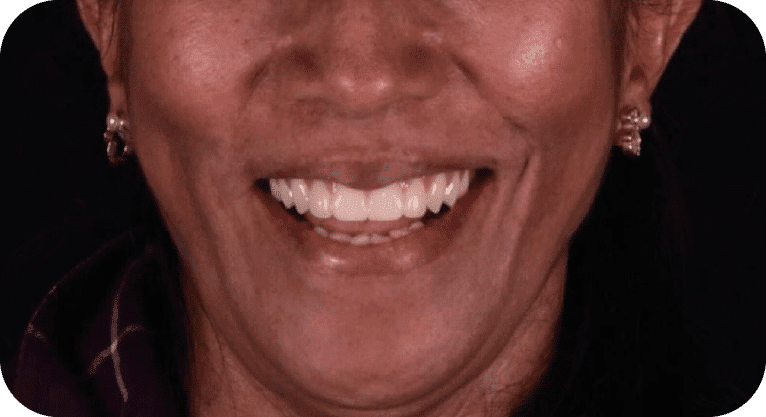

Paciente femenino, “52” años

Tratamiento: All of 4

La paciente acudió a la clínica tras perder varios dientes superiores por caries, utilizando una prótesis removible que le resultaba incómoda; deseaba una solución fija, por lo que se le realizó una rehabilitación completa con técnica All-on-4, colocando 4 implantes dentales que soportan una prótesis fija, devolviéndole la funcionalidad, seguridad y una sonrisa natural de forma permanente.